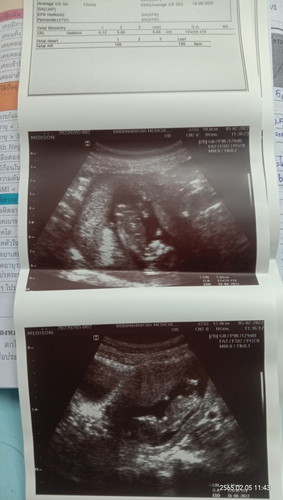

แม่ๆช่วยดูเพศให้หน่อย..ว่าตรงตามที่คุณหมอบอกไหม แอบผิดหวังนิดนึงแต่ก็ดีใจค่ะลูกแข็งแรงสมบูรณ์

อายุครรภ์11w+3d

คุณหมอบอกผช.เห็นมีจู๋แต่แม่อยากได้ผญ.ภาวนาขอให้หมอดูผิด😅

ผญ.มั้ยคะ 🙃